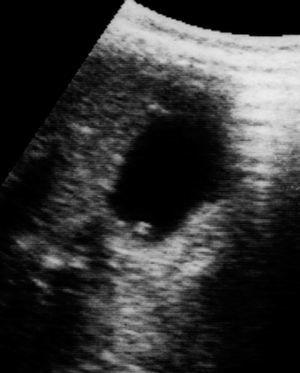

Una niña de 12 años, con antecedentes de nefrectomía izquierda por riñón multiquístico, fue derivada a nuestro servicio por haberse visualizado en una ecografía abdominal, realizada rutinariamente como seguimiento de su patología de base, una lesión polipoidea de 3 mm de diámetro en el fundus de la vesícula biliar. La paciente no tenía síntomas digestivos. Tanto el hemograma como el perfil hepático y la amilasa sérica fueron normales. La exploración física no mostró hallazgos reseñables. En nuestro centro, se repitió la ecografía abdominal, que confirmó la imagen descrita (fig. 1). Se ha optado con respecto a la paciente una actitud conservadora y expectante, a través de la realización de ecografías abdominales seriadas con periodicidad anual.

Figura 1. Lesión polipoidea en el fundus de la vesícula biliar.

Las lesiones polipoideas de la vesícula biliar se suelen diagnosticar a través de ecografía abdominal 2. Esta prueba diagnóstica tiene una sensibilidad y una especificidad mayores del 90 %. La generalización del uso de esta técnica facilitará que, en un futuro, se lleguen a diagnosticar más casos en la edad pediátrica. Las lesiones polipoideas de la vesícula biliar se visualizan como lesiones redondeadas, pediculadas o sesiles, que no varían con los cambios de posición, que se muestran adheridas a las paredes de la vesícula, protruyen hacia la luz vesicular y dejan sombra posterior. En todos los casos descritos en pacientes pediátricos, las lesiones eran únicas. En cuanto al diagnóstico diferencial, debe ser distinguido de las imágenes correspondientes a litiasis y a coágulos de sangre.